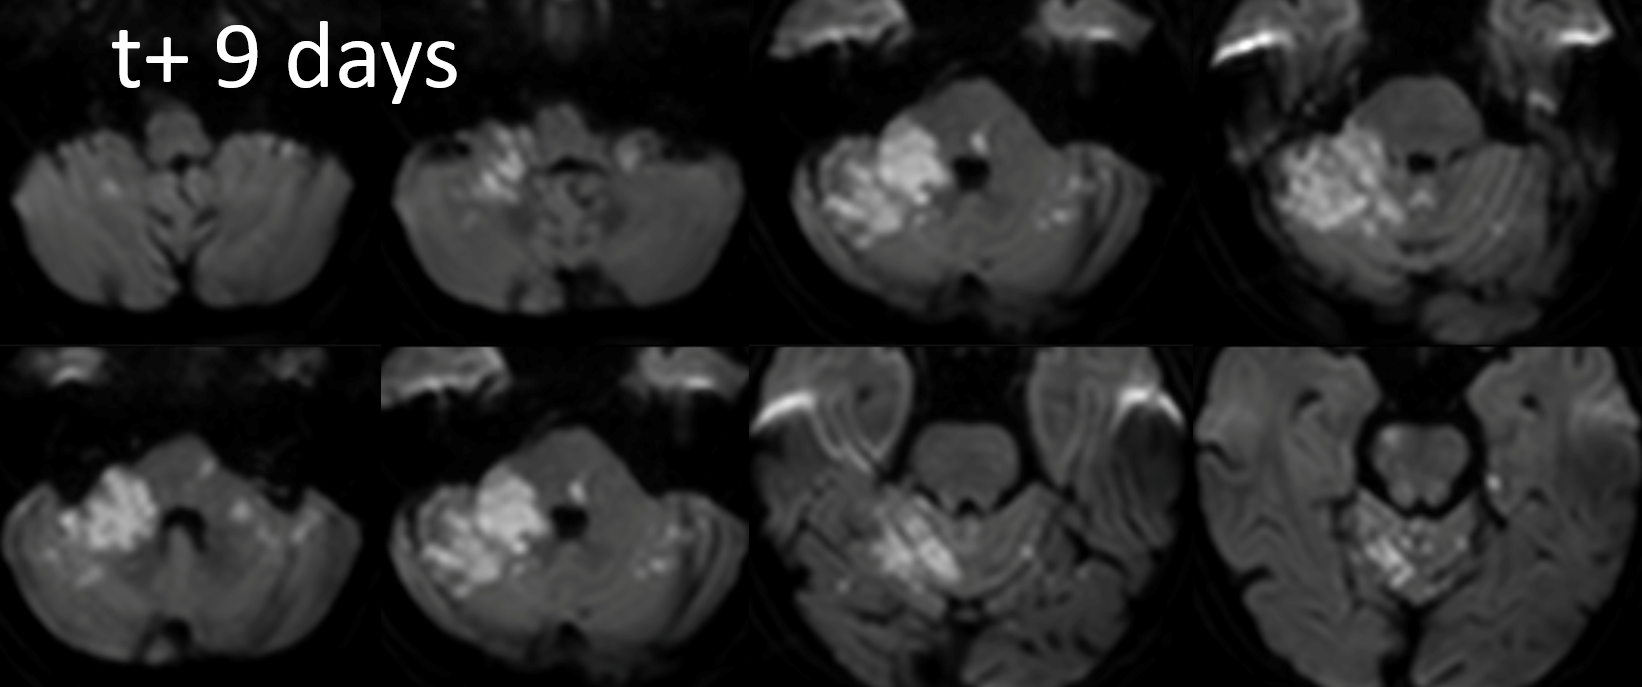

Another awesome vasa vasorum case by Guglielmo Pero MD

First angio

Small right PCOM

Unsuccessful Recan attempt